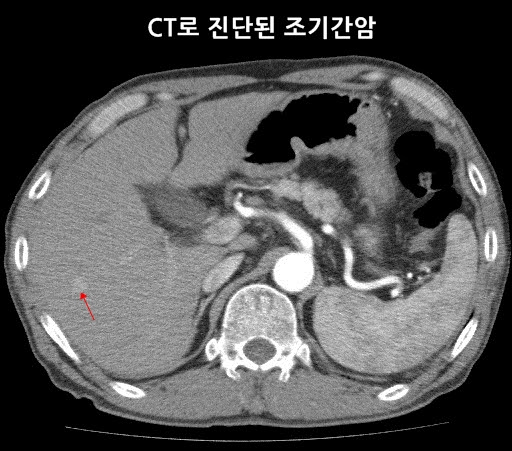

- 간암: 간 내 종양의 형성은 CT에서 명확하게 확인될 수 있으며, 조기 발견이 치료에 중요한 영향을 미칩니다.